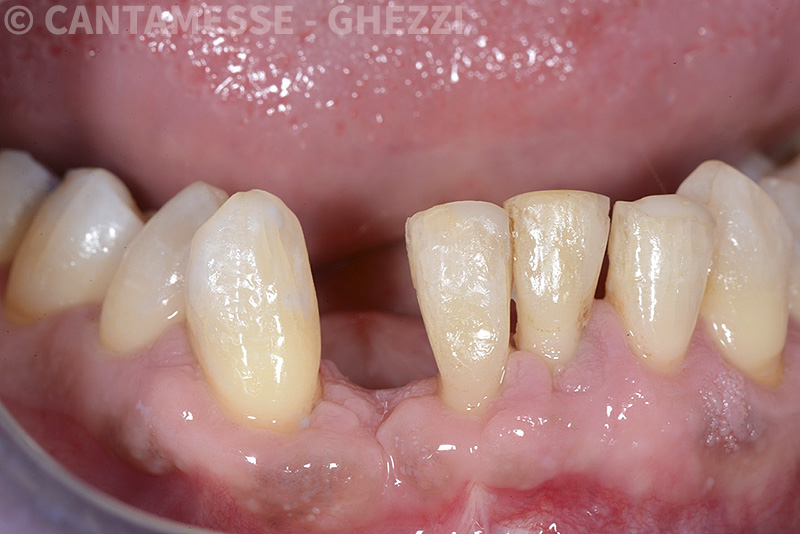

PREMESSA: in seguito all’estrazione dell’incisivo laterale superiore di destra, resasi necessaria per cause batteriche, si decide di affrontare il caso con il posizionamento di un impianto in sostituzione dell’elemento mancante dopo guarigione del sito infetto. Con tecniche rigenerative sia dei tessuti ossei mancanti a causa dell’infezione pregressa, sia dei tessuti gengivali che appaiono inizialmente troppo spostati in alto, si ripristina una corretta morfologia delle parabole (contorni) gengivali e delle papille interdentali (triangoli di gengiva tra due denti vicini).

Vengono utilizzati 2 tipi di provvisori: il primo, cementato ai denti vicini, viene utilizzato dal momento dell’estrazione del dente fino ad impianto osteointegrato (circa 6 mesi); il secondo, avvitato direttamente all’impianto, ha una funzione di prova estetica ma soprattutto di guida per la maturazione dei tessuti gengivali peri-implantari portandoli verso la maturazione completa prima di posizionare la corona finale in disilicato di litio.